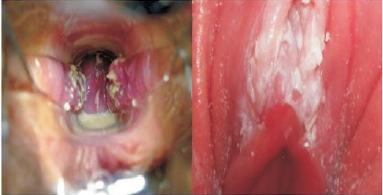

Mulher no menacme procura o ginecologista na UBS. Ao exame físico, o médico encontrou o seguinte cenário.

enunciado 1107875-1

Qual o achado mostrado pela foto?